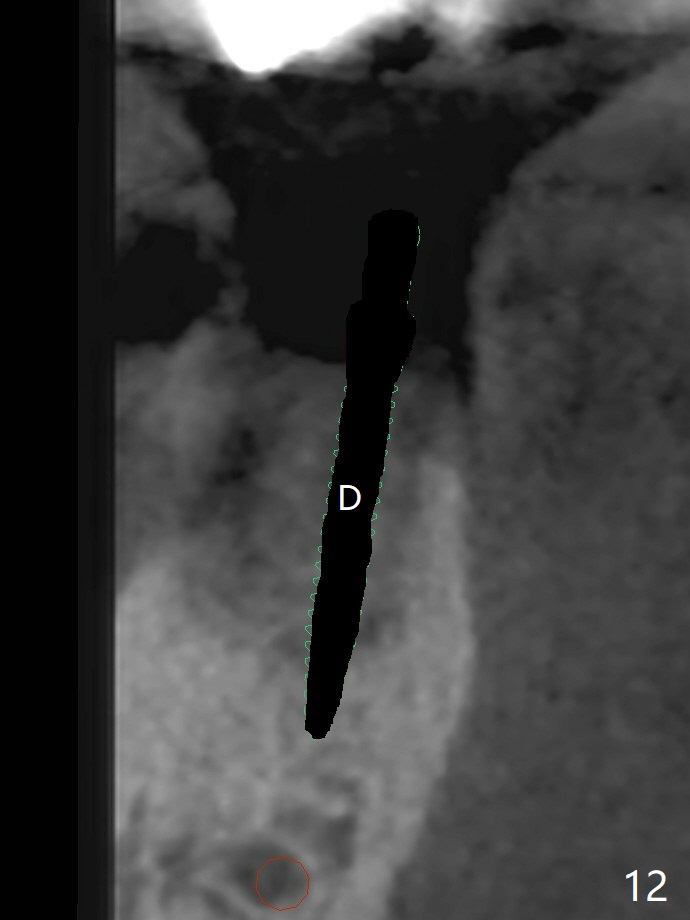

A 88-year-old man returns with pain and swelling (Fig.1), one year after diagnosis of #31 mesial root fracture. After discussion, the tooth is extracted with socket preservation (Vanilla graft mixed with Osteogen, covered with Osteogen plug and Collagen plug, Fig.2,3). The buccal crest is much lower than the lingual one. The socket opening reduces with resolution of 4-0 Chromic gut suture 1 week postop (Fig.4). The wound is wider with foul odor 2 weeks postop (data not shown). The socket and ridge shrink with loss of the bone graft 3 weeks postop (Fig.5). The bone volume reduces with buccal plate collapse 3 months postop (Fig.6,7). Immediate implant and provisional should be able to help restore the lost buccal plate. The buccal plate remains concave 5 months postop (Fig.8,9). The coronal section shows that there is space (Fig.10 *) buccal to the graft (G). A 2.0 mm pilot drill is used to create an initial osteotomy through the graft zone and in the beginning of the native bone (Fig.11,12). Use bone expanders (Fig.13 E) to push (arrowheads) and condense the graft bone and close the buccal gap. The apical portion of the osteotomy requires regular drills (Fig.14 D).